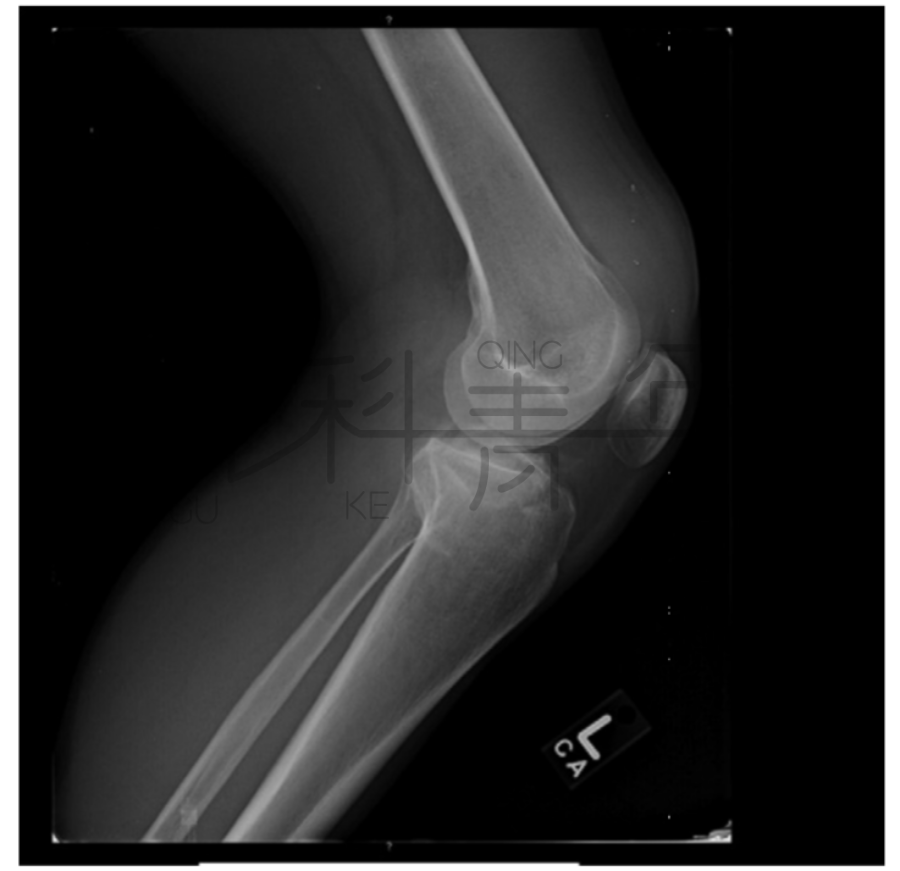

病例3一例膝关节外伤患者,在膝关节侧位X线上,积脂血症并不明显。